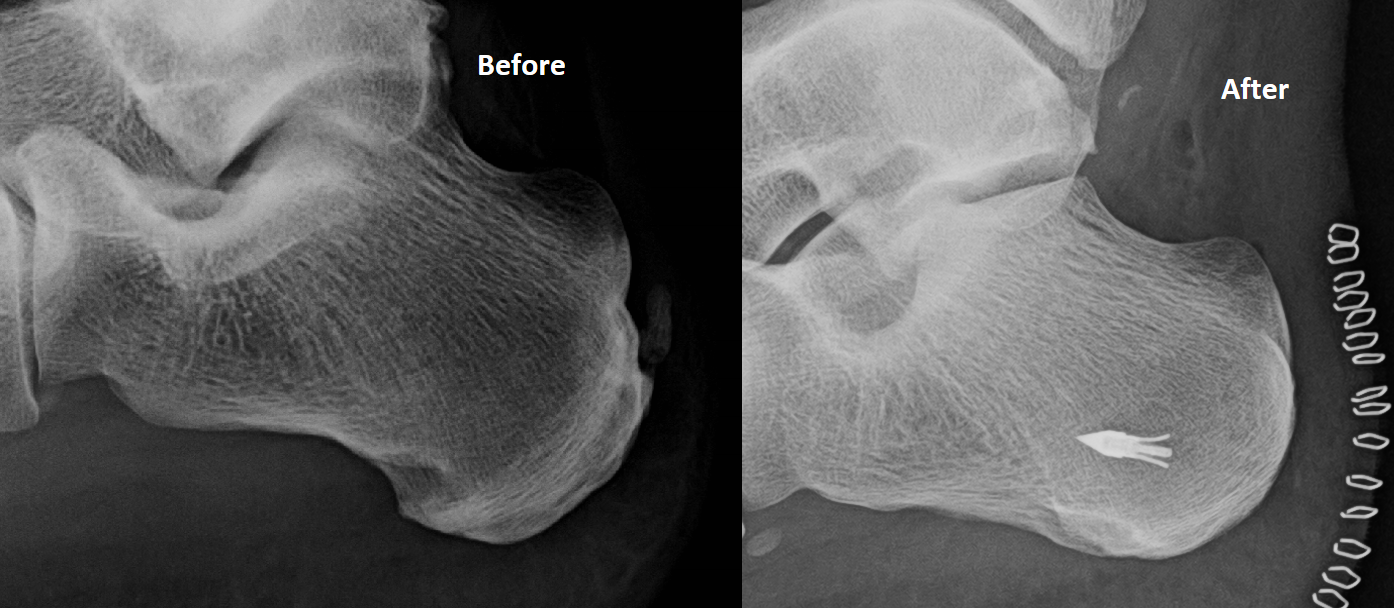

Postop xray of a bone spur removal from the back of the heel Bone Remove Bone Spur Without Surgery Tell your healthcare provider if you develop. understanding bone spurs and why they occur is essential to learning how to dissolve bone spurs naturally. Lean toward the wall, allowing your left knee to. Face the wall a few feet back with your left foot in front of your right foot. Taking apple cider vinegar each day is said. . Remove Bone Spur Without Surgery.